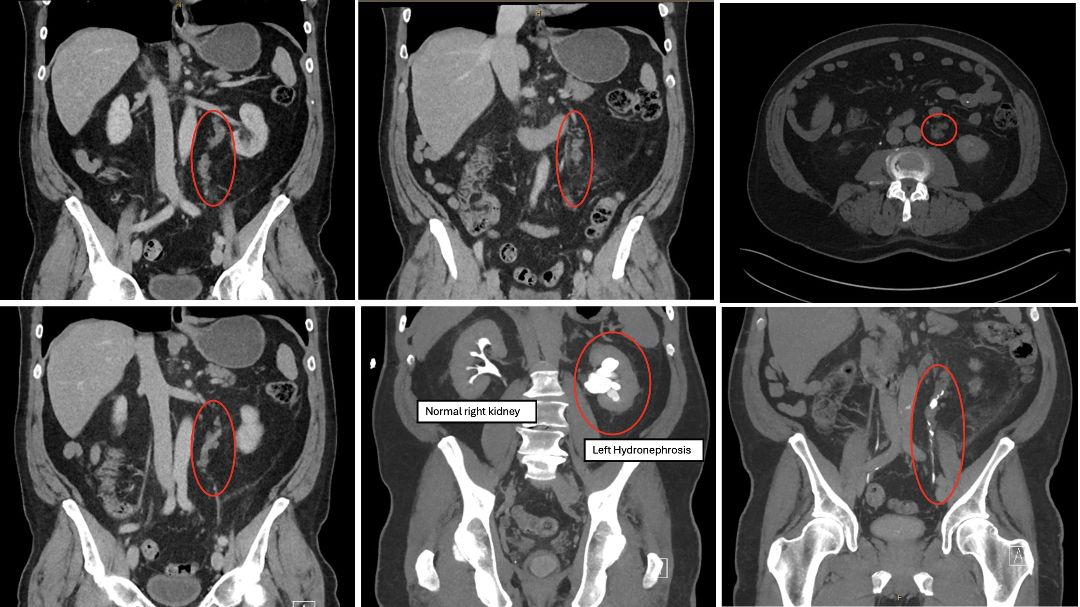

However, at 10 years post-recurrence, CT of upper tracts demonstrated moderate left pelvicalyceal dilatation with pelvi-ureteric junction obstruction due to appearance of fairly extensive lobular enhancing and thickened upper ureter over craniocaudal extent of 90mm. Additionally, periureteric nodular soft tissue observed which were anticipated to be enlarged lymph nodes versus direct extension in the anteromedial renal fascia measuring up to 7mm (Figure 1). On the delayed phase there was stasis of contrast in the dilated pelvicalyceal system without opacification of the left ureter, raising suspicion of obstructive pathology.

Figure 1 Left periureteric soft tissue density and left hydronephrosis